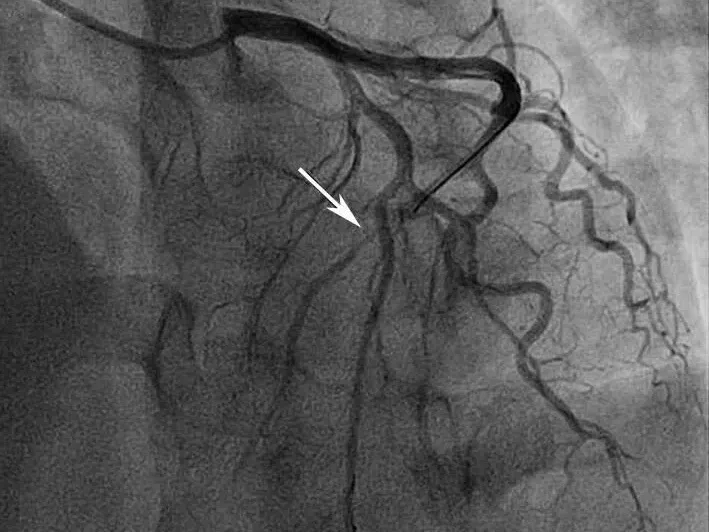

给予双联抗血小板、调脂、控制心率、抗心衰及泼尼松龙60mg每日1次,并皮下注射依诺肝素强化抗凝,1周后复查心脏超声(图2),发现右房内疑似血栓影完全消失,患者也无低氧、咯血等肺栓塞临床表现。后完成CAG +光学相干成像(OCT)检查(图3),提示:左优势型,前降支近段管腔不规则发白,考虑血栓影,管腔分支稀少,血流TIMI 3级;回旋支远段节段性狭窄达90%,血流TIMI 2级;右冠细小。

图3 冠脉造影结果

A图显示前降支血流稍慢,中段可见管腔发白,怀疑血栓影;B图提示回旋支远段重度狭窄90%,血流TIMI 2级

在患者心衰症状得到有效控制后,我们为其进行了冠状动脉造影联合光学相干断层成像(OCT)检查。结果显示前降支内仍存在血栓,近段前降支及左主干可见不稳定斑块,并存在斑块侵蚀与原位血栓形成的证据。后续通过右心声学造影检查,排除了矛盾栓塞的可能。至此,临床诊断支持“二元论”解释,治疗方案也据此双线展开:一方面针对冠心病与心力衰竭,给予双联抗血小板、他汀类药物及利尿剂联合“金三角”抗心衰治疗;另一方面针对肾病综合征与高凝状态,先后予以低分子肝素皮下注射与口服达比加群抗凝,并辅以激素冲击治疗。经上述综合干预,患者右心耳血栓消失,胸闷气短症状显著缓解,心率、血压趋于稳定,活动耐力明显改善,病情好转出院。